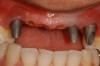

Figure 11 – Internal connection implant system – implant placed post-extraction

Figure 11

Figure 12 – Prefabricated zirconia abutment fitting the internal connection in Figure 11

Figure 12

Figure 13 – Zirconia abutment torque onto implant

Figure 13